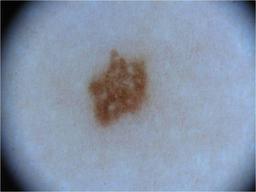

{

"age_approx": 30,

"anatom_site_general": "upper extremity",

"concomitant_biopsy": false,

"diagnosis_1": "Benign",

"diagnosis_2": "Benign melanocytic proliferations",

"diagnosis_3": "Nevus",

"diagnosis_4": "Nevus, Atypical, Dysplastic, or Clark",

"diagnosis_5": "Nevus, Dysplastic",

"image_type": "dermoscopic",

"melanocytic": true,

"sex": "male"

}